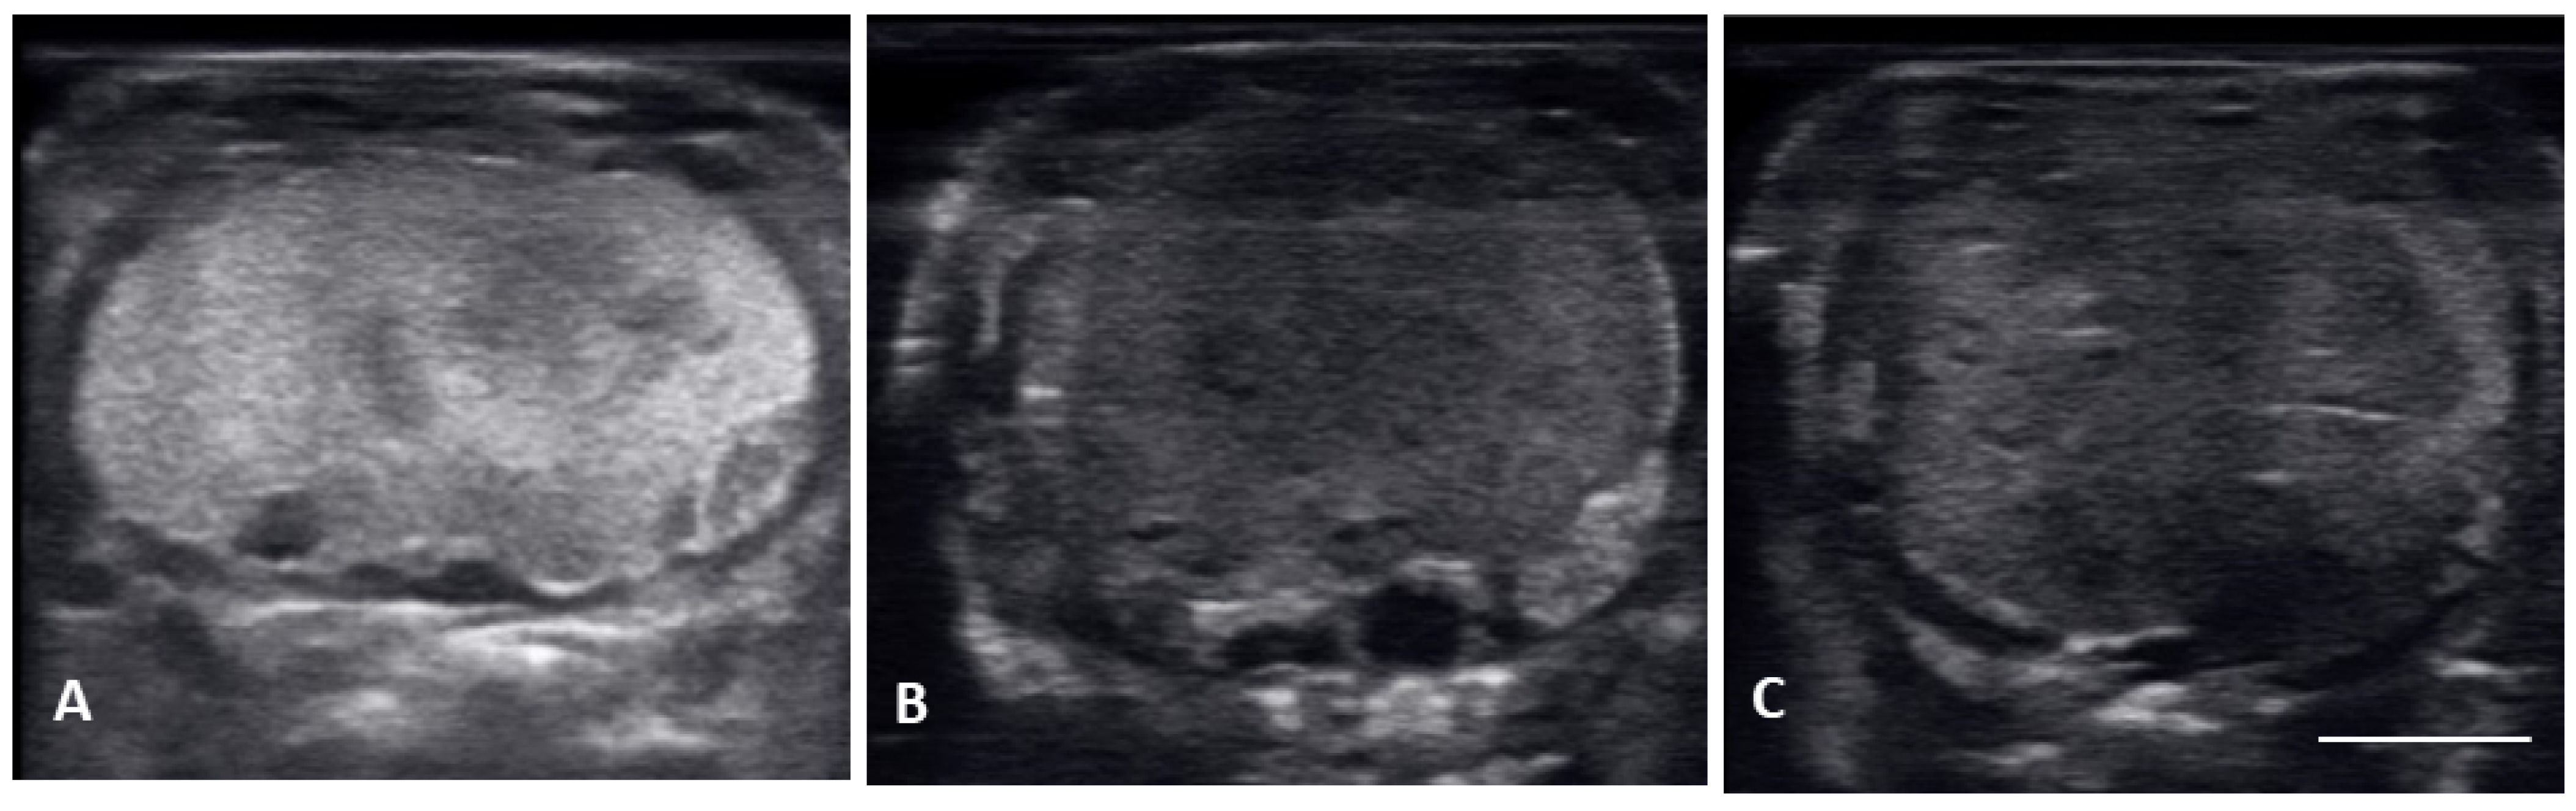

| Peri-ovulatory follicles (PERI) | Elongated follicles, mostly homogenous hyperechoic structure with thick hypoechoic outline. Before female is overtly swollen. |

| Post ovulatory follicles (POV) | Ovulated follicles, passed into the oviduct showing an hypoechoic surrounding, but no visible calcified layer. |

| Shelled eggs (Shell) | Ovulated follicles, passed into the oviduct and surrounded by a calcified layer. |